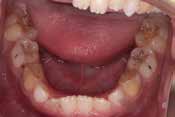

Before

下の奥歯が内側に傾いて、舌の位置が悪く、鼻がつまって口呼吸の状態でした。扁桃腺がよく腫れ、風邪をひきやすく、いびきもあるようでした。

治療を終えて

装置で上あごを拡大し、下の歯の位置を整え、前歯の並びを整えました。お口のトレーニングの効果で鼻詰まりと、いびきも改善。たった1年でこの変化が見られました。もちろん歯は1本も抜いていません。

主訴・治療内容 他院にて「抜歯した上で、ワイヤーを付け、5年かけて治療する」と言われ、他の方法はないのかとネットで調べたところ、当院を知り無料相談に来院されました。

治療期間 1年

費用 462,000円(税込)